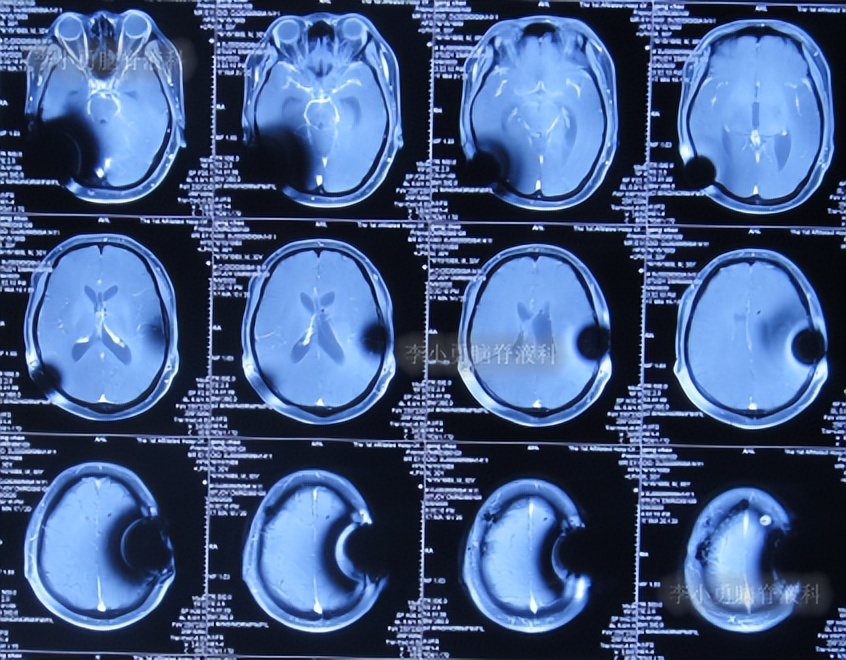

术后患者症状慢慢缓解,但腰椎穿刺检查示脑脊液蛋白非常高,患者虽神志清楚,可是下颌不自主震颤,伴有复视。

第2次的左侧脑室腹腔分流术后10天即2020年1月10日,查头颅CT示脑室仍有扩张(图-7)。

图-7:2020年1月10日头颅CT

第2次的左侧脑室腹腔分流术后18天即2020年1月18日,查头颅CT示脑室有缩小(图-8)。

图-8:2020年1月18日头颅CT

第2次的左侧脑室腹腔分流术后38天即2020年2月7日,查脊髓核磁示未见明显异常(图-9)。

图-9:2020年2月7日脊髓核磁

第2次的左侧脑室腹腔分流术后40天即2020年2月9日,查头颅核磁示脑室稍有扩张(图-10)。

图-10:2020年2月9日头颅核磁

第2次的左侧脑室腹腔分流术后44天即2020年2月13日,查头颅核磁示脑室较2020年2月9日有扩张(图-11),未给予特殊处理。

图-11:2020年2月13日头颅核磁

第4次在该院治疗2个月即2020年2月28日出院,但仍有视物模糊。

第4次出院后2个月时间内,期间曾4次查头颅影像均示脑室有进一步扩张(图-12、图-13、图-14、图-15),且患者精神逐渐变差。

图-12:2020年3月14日头颅CT

图-13:2020年3月31日头颅核磁

图-14:2020年4月18日头颅CT

图-15:2020年5月9日头颅核磁

第5次住院治疗

第4次出院后2个半月即2020年5月14日,患者意识变差,且不能下地活动,第5次就诊于给予手术的医院,查头颅CT示脑室扩张加重(图-16)。

图-16:2020年5月14日头颅CT

第5次在该院治疗20天,期间2次查头颅CT示脑室有所缩小(图-17、图-18)。

图-17:2020年5月21日头颅CT

图-18:2020年5月25日头颅CT

第5次住院治疗21天后即2020年6月4日,因患者意识仍差,当地的一位医生好心的建议可以到北京的李小勇脑脊液科试试。

二、第1次在李小勇脑脊液科治疗过程和结果

2020年6月4日(脑囊虫切除术+第三脑室造瘘术后2年5个月,2次脑室腹腔分流术均堵管,期间历经5次住院但脑积水仍反复复发)住入李小勇脑脊液科,入院时:神志朦胧,饮食差,问答有误,自己站立不稳,双眼对视(图-19);既往史:口服抗癫痫药物,青霉素过敏。头颅CT示鞍上占位术后,脑室内可见引流管,脑室系统扩张(图-20)。

图-19:2020年6月4日入院时

图-20:2020年6月4日头颅CT